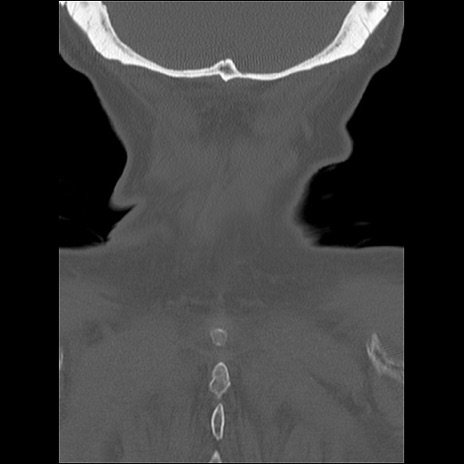

症例48 頚椎CT(冠状断像)

頚椎CT